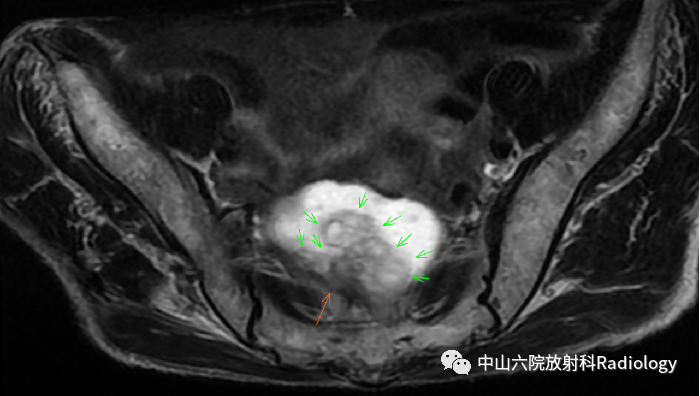

MRI表现

直肠充盈后T2WI(斜轴位)

直肠MRI(平扫-常规序列)

直肠MRI(DWI+增强)

定位 数量 形态 大小 信号 边缘 强化 淋巴 远处

MRI印象:直肠黏液腺癌?